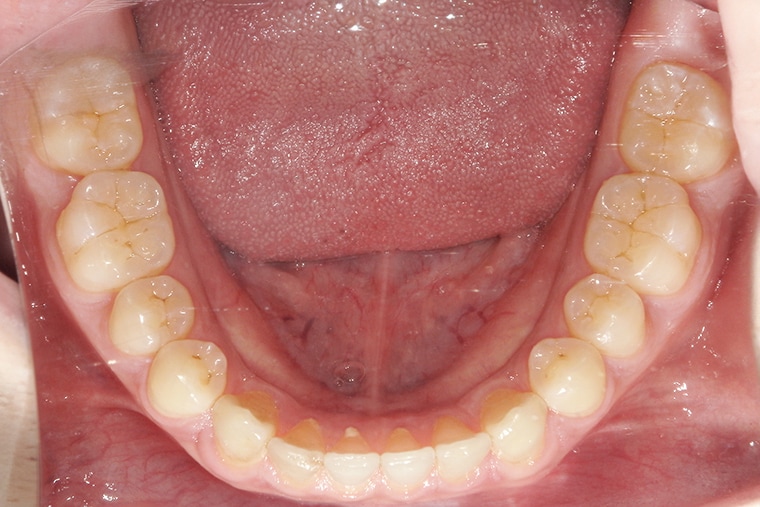

Case Study18歳男性すきっ歯のマウスピース矯正-矯正期間6ヶ月(2024年8月開始)